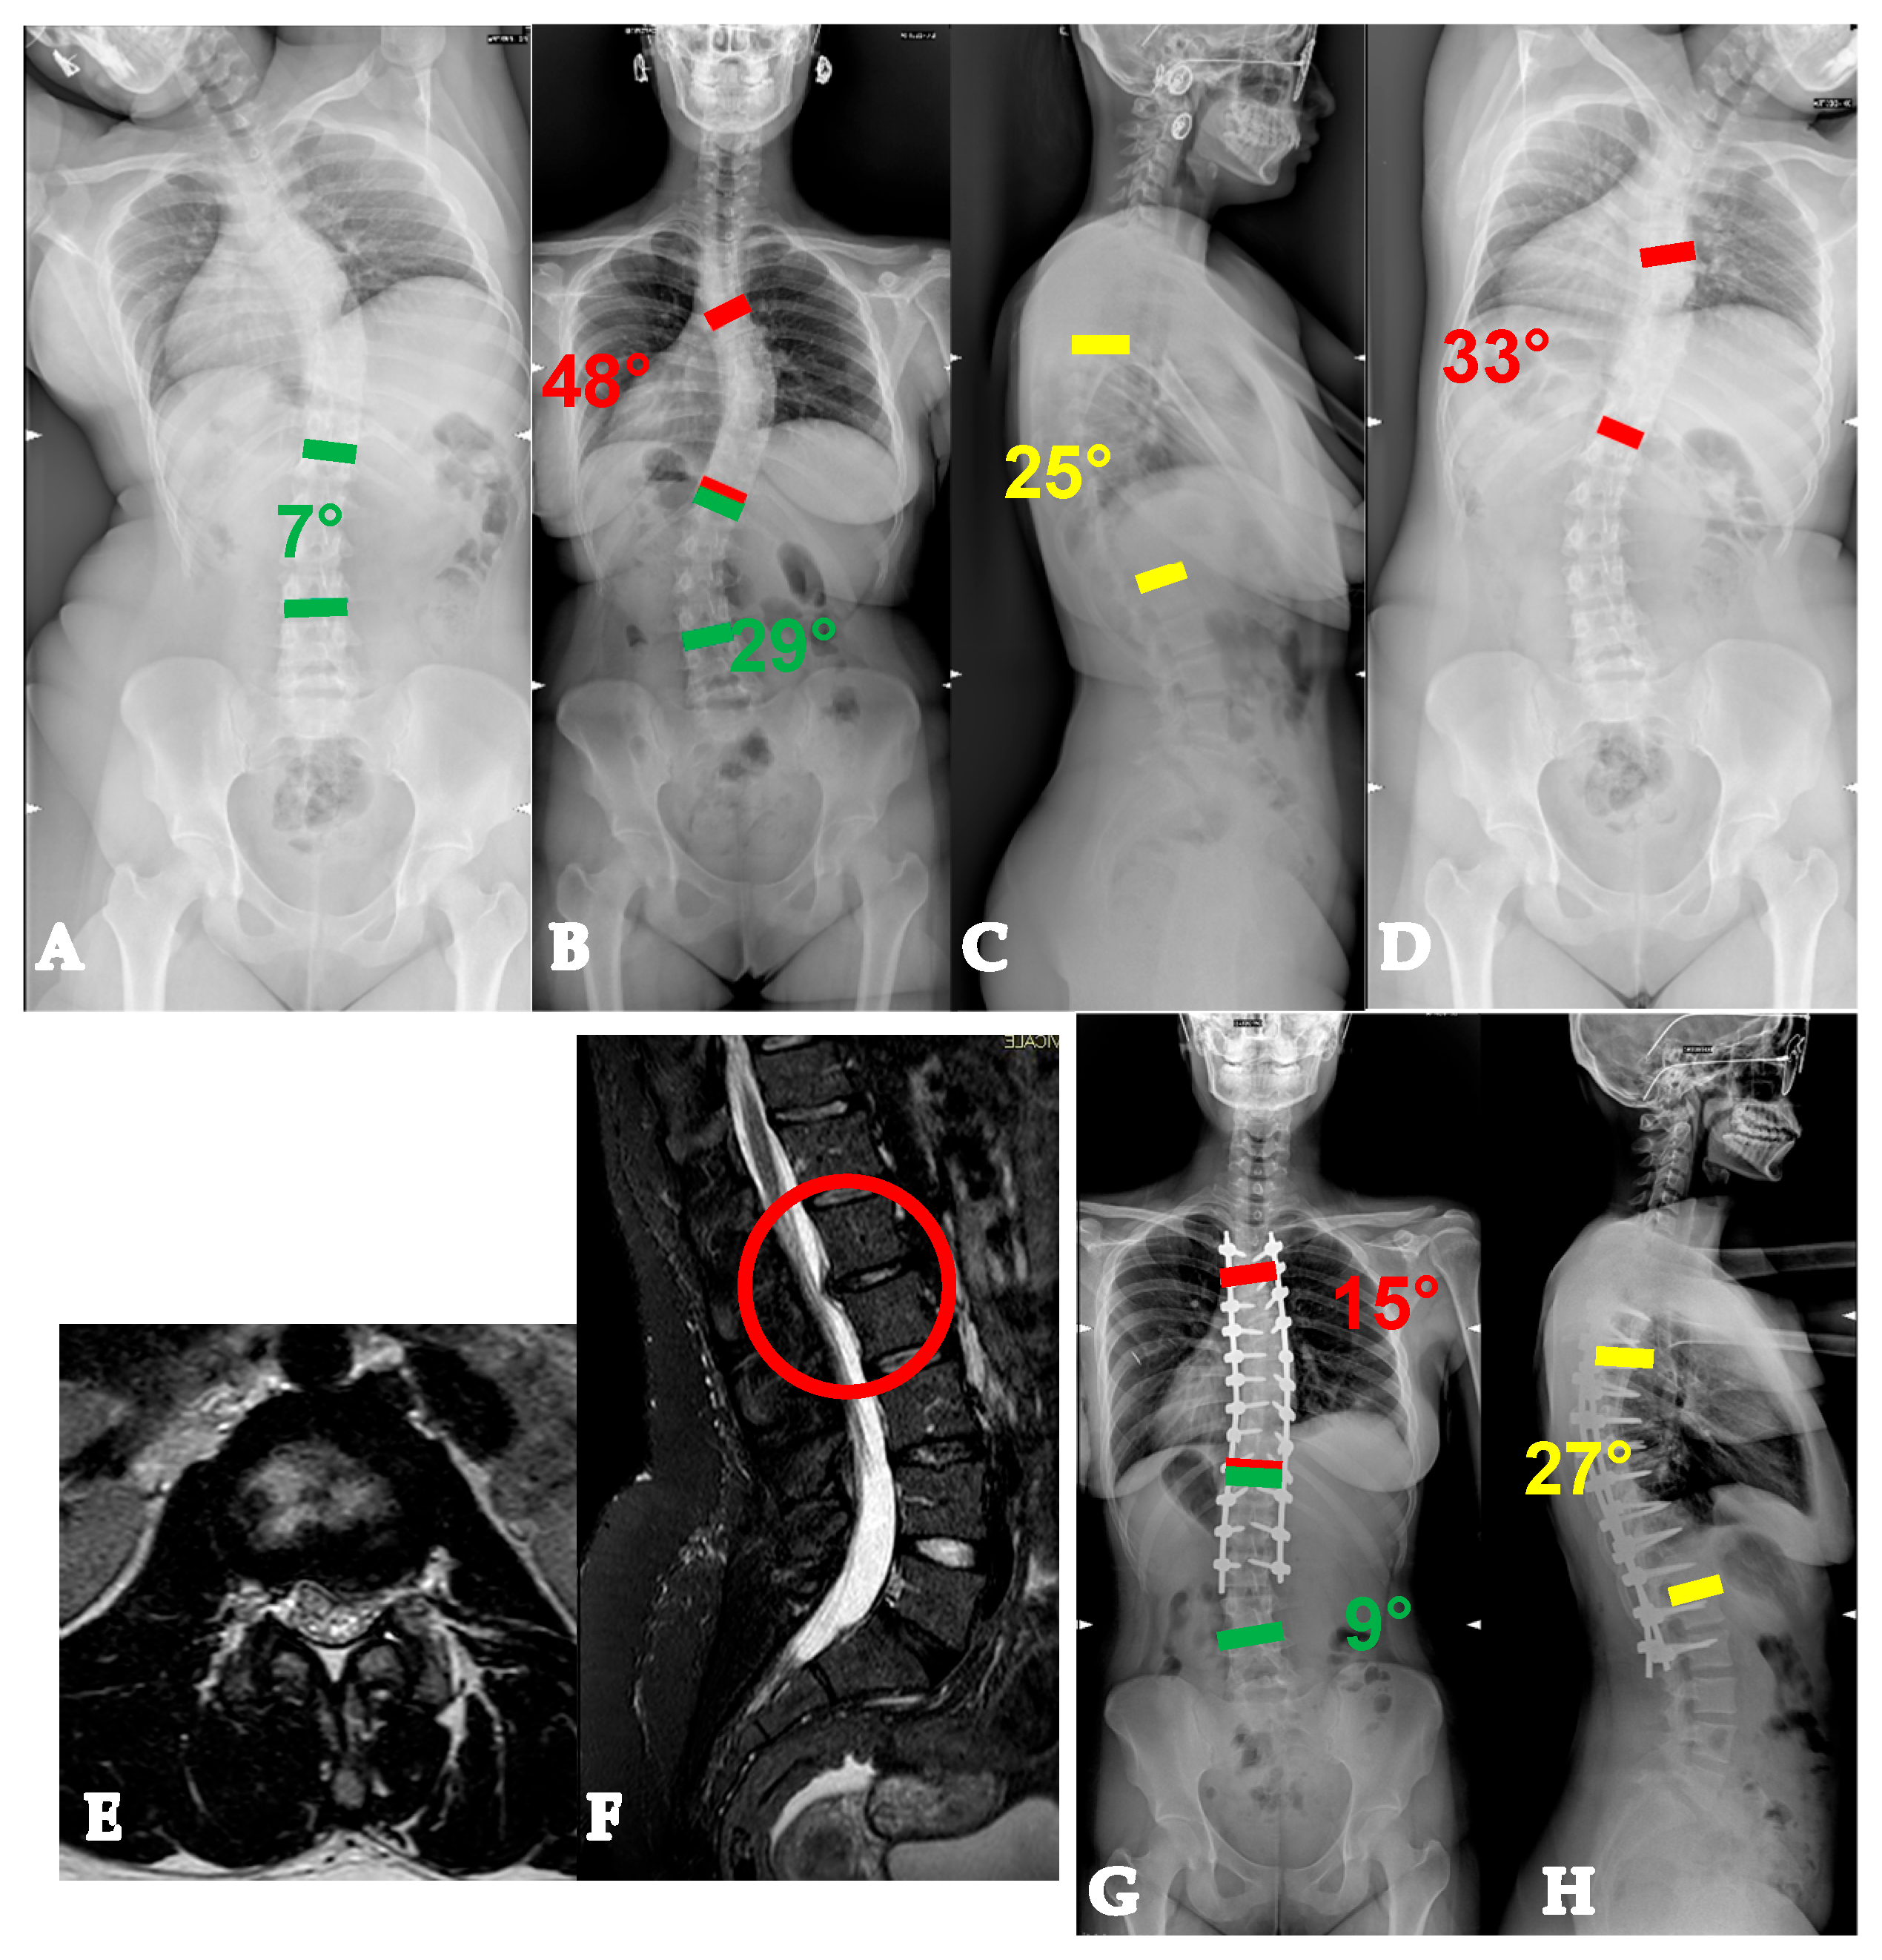

- AdIS 1B: 45–60 years old. These patients usually have a stiffer main curve, with the not infrequent presence of anterior column osteophytes, especially at the concave side. In this setting, combined corrective strategies based on posterior releases (Hi-PoAD [10]) can still achieve an optimal translation, but often, derotation potential is limited, with a possible residual of a partial rib hump (Figure 6).